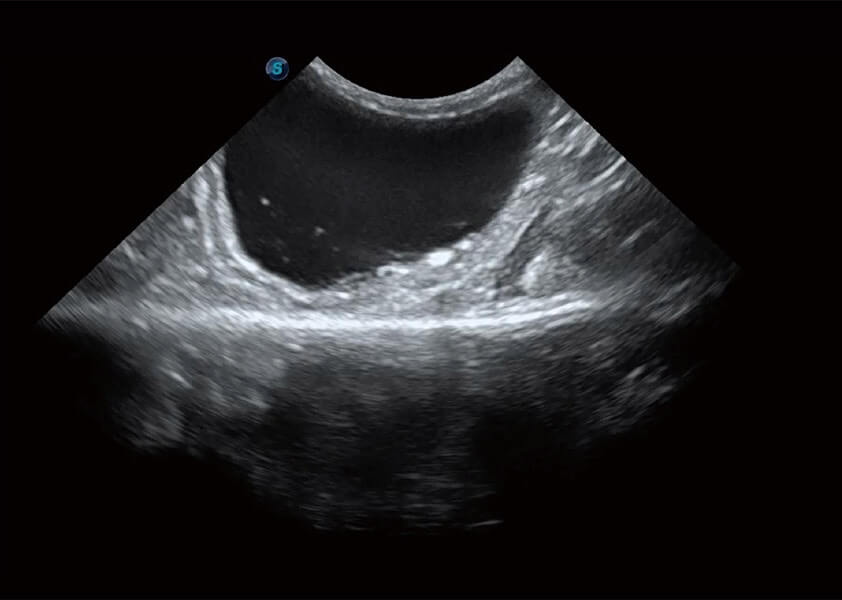

ProPet 60 作為一款高端臺(tái)式動(dòng)物超聲設(shè)備,為動(dòng)物醫(yī)生的日常診斷提供了一系列貼合動(dòng)物臨床需求、解決臨床實(shí)際問題的高級成像功能。憑借全系列高清探頭,滿足醫(yī)生對腹部、心臟、生殖、淺表、肌骨等成像的所有需求,切實(shí)幫助您提升檢查效率,提高診斷信心。